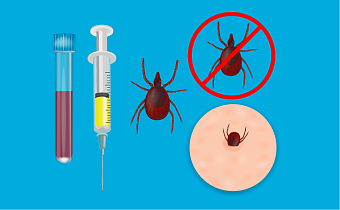

Острое инфекционное заболевание, которое передается через укус иксодового клеща, зараженного бактерией Anaplasma phagocytophilum.

7 минут

6362

5

15.05.2026

Острое инфекционное заболевание, вызываемое бактериями рода Ehrlichia, которое передается через укус клеща и поражает преимущественно моноциты.

7 минут

5833

4

15.05.2026

Инфекционное заболевание, вызванное простейшими паразитами рода Babesia, которые передаются через укус иксодового клеща.

7 минут

342

3

Инфекционное заболевание, которое передается человеку через укус иксодового клеща и поражает кожу, нервы, суставы и сердце.

7 минут

21598

17

Укус клеща может закончиться опасными инфекциями: клещевым энцефалитом, боррелиозом, анаплазмозом, эрлихиозом. Если заметили паразита на себе, нужно действовать быстро.

9 минут

27511

8

Две самые частые инфекции, которые передаются человеку при укусе иксодового клеща и имеют характерные проявления.

12 минут

19064

5

Клещевой энцефалит может привести к тяжелым поражениям нервной системы и даже инвалидности. Но защита есть, и это — вакцинация.

10 минут

7498

1